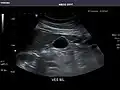

Left kidney -